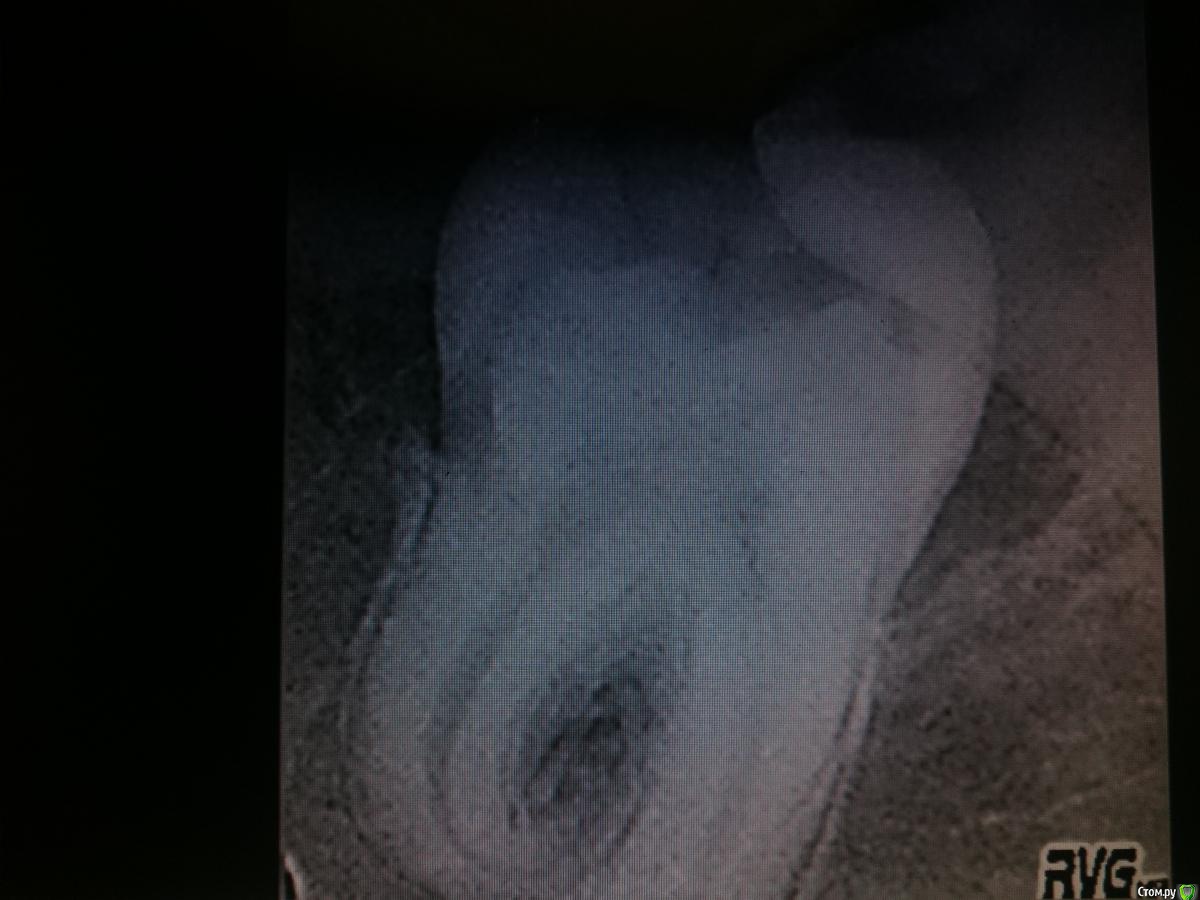

АнтонТЛТ Опубликовано 24 ноября, 2016 Поделиться Опубликовано 24 ноября, 2016 47 зуб http://i84.fastpic.ru/big/2016/1124/a0/1dcd852c008f04a8ebd63abd21ac6ea0.jpg Напомнило))) http://i84.fastpic.ru/big/2016/1124/99/6895a7f344bb1057796fd898bf5c1099.jpg 12 Ссылка на комментарий

Большой Зеленый Опубликовано 24 ноября, 2016 Поделиться Опубликовано 24 ноября, 2016 47 зуб Напомнило))) Он горизонтально лежал? Корнем вверх в полость рта? Ссылка на комментарий

diesel87 Опубликовано 24 ноября, 2016 Поделиться Опубликовано 24 ноября, 2016 Нет, обычноА что это за рифы на нем? Ссылка на комментарий

АнтонТЛТ Опубликовано 24 ноября, 2016 Поделиться Опубликовано 24 ноября, 2016 А что это за рифы на нем?Он решил стать пиратом)))(Поддесневой камень) 4 Ссылка на комментарий